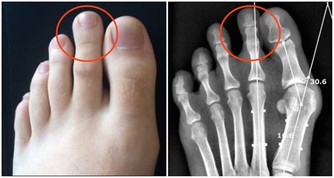

■懶事三:懶得運動,骨質變鬆。

△健康影響:人老了本來就不愛動,加上腿腳不好,很多人會懶得運動,甚至兩三天都不下一次樓。如果長期不運動,人的肌肉會變萎縮,骨關節力量變弱,血液循環減慢,增加骨折、骨關節炎、血栓等風險;不愛動還可能讓老人變胖,而超重和肥胖更會增加「三高」風險,並且,患心腦血管疾病和大腸癌的幾率會增加2~5倍。

△調節方法:經常鍛煉有助預防骨質疏鬆,強健骨骼、肌肉;運動還有益於大腦健康,預防老年癡獃,改善糖尿病、心臟病等多種慢病。